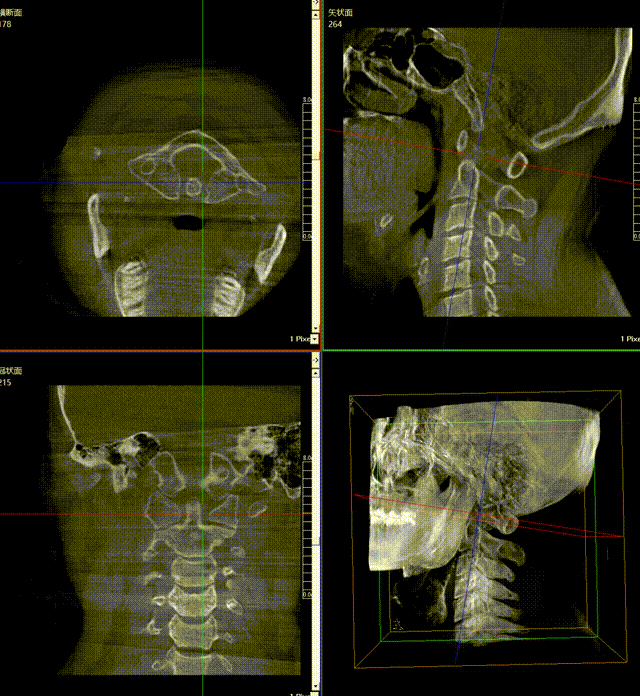

通常上頸椎的手術是非常復雜的,因為醫生要把釘子打在上頸椎這樣一個很狹小的通道里面,周圍都是重要的神經血管,一旦損傷到頸椎,就有可能造成病人的死亡。隨著醫學影像技術的不斷發展,在三維影像的引導下,整個打進去的通路能夠完全的展現在我們的眼睛里,讓這種復雜的手術變得簡單了,更多的醫生就可以去開展這樣的手術了,也會有越來越多的病人從中獲益。